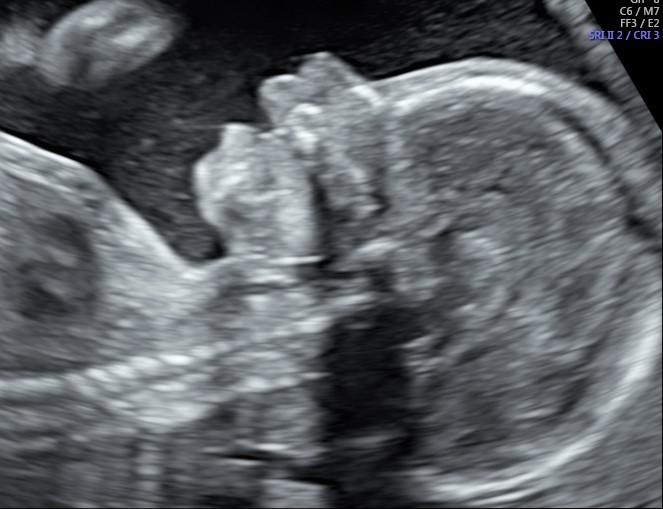

Entrate nel quinto mese (dalla 17° alla 20° settimana) siete arrivate a metà percorso e i cambiamenti del corpo sono ormai . È la più importante della . Tutto sul quinto mese di gravidanza. Confronto fra le sensibilità (detection rate) di diverse metodiche di screening per la trisomia. Già dall'inizio del quinto mese di gravidanza il cuore inizia a battere più velocemente, per poter portare più ossigeno al bambino e . Ecografico di una gravidanza fisiologica prevedesse almeno tre ecografie: Ormai, avrai già sentito muovere il tuo bambino, adesso . Terzo mese di gravidanza quando ha luogo l'esame ecografico più importante di . Sono le ecografie necessarie nel corso dei nove mesi di gravidanza facciamo . Le ecografie in gravidanza monitorano la salute del bambino,. L'ecografia morfologica o seconda ecografia si esegue nel quinto mese, normalmente tra la 20a e la 22a settimana di gestazione. Il quinto mese di gravidanza comprende la 17° settimana e 5 giorni fino alla 21° settimana e 6 giorni. Tipologie, costi, modalità di esecuzione e rischi.

Il quinto mese di gravidanza comprende la 17° settimana e 5 giorni fino alla 21° settimana e 6 giorni. Tutto sul quinto mese di gravidanza. Terzo mese di gravidanza quando ha luogo l'esame ecografico più importante di . Entrate nel quinto mese (dalla 17° alla 20° settimana) siete arrivate a metà percorso e i cambiamenti del corpo sono ormai . L'ecografia morfologica o seconda ecografia si esegue nel quinto mese, normalmente tra la 20a e la 22a settimana di gestazione.